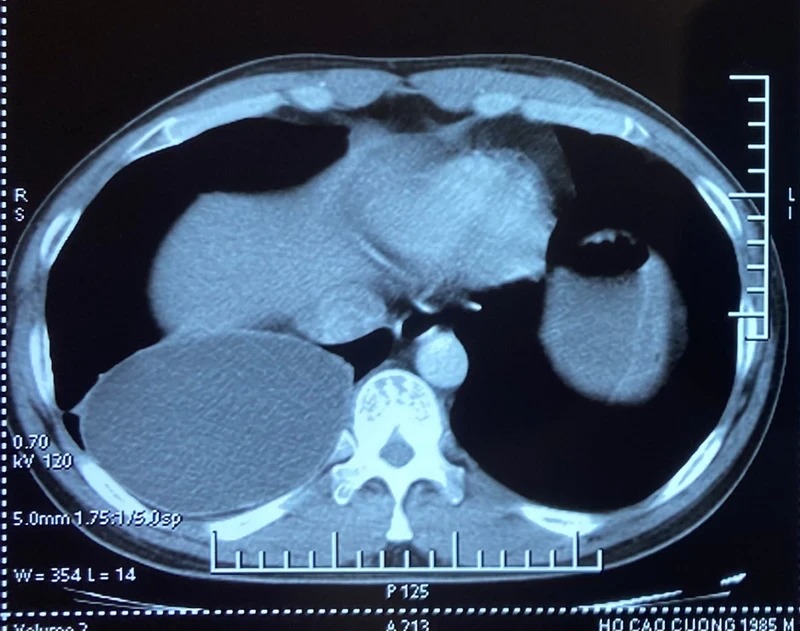

Ấu trùng sán dây chó ký sinh tại phổi.